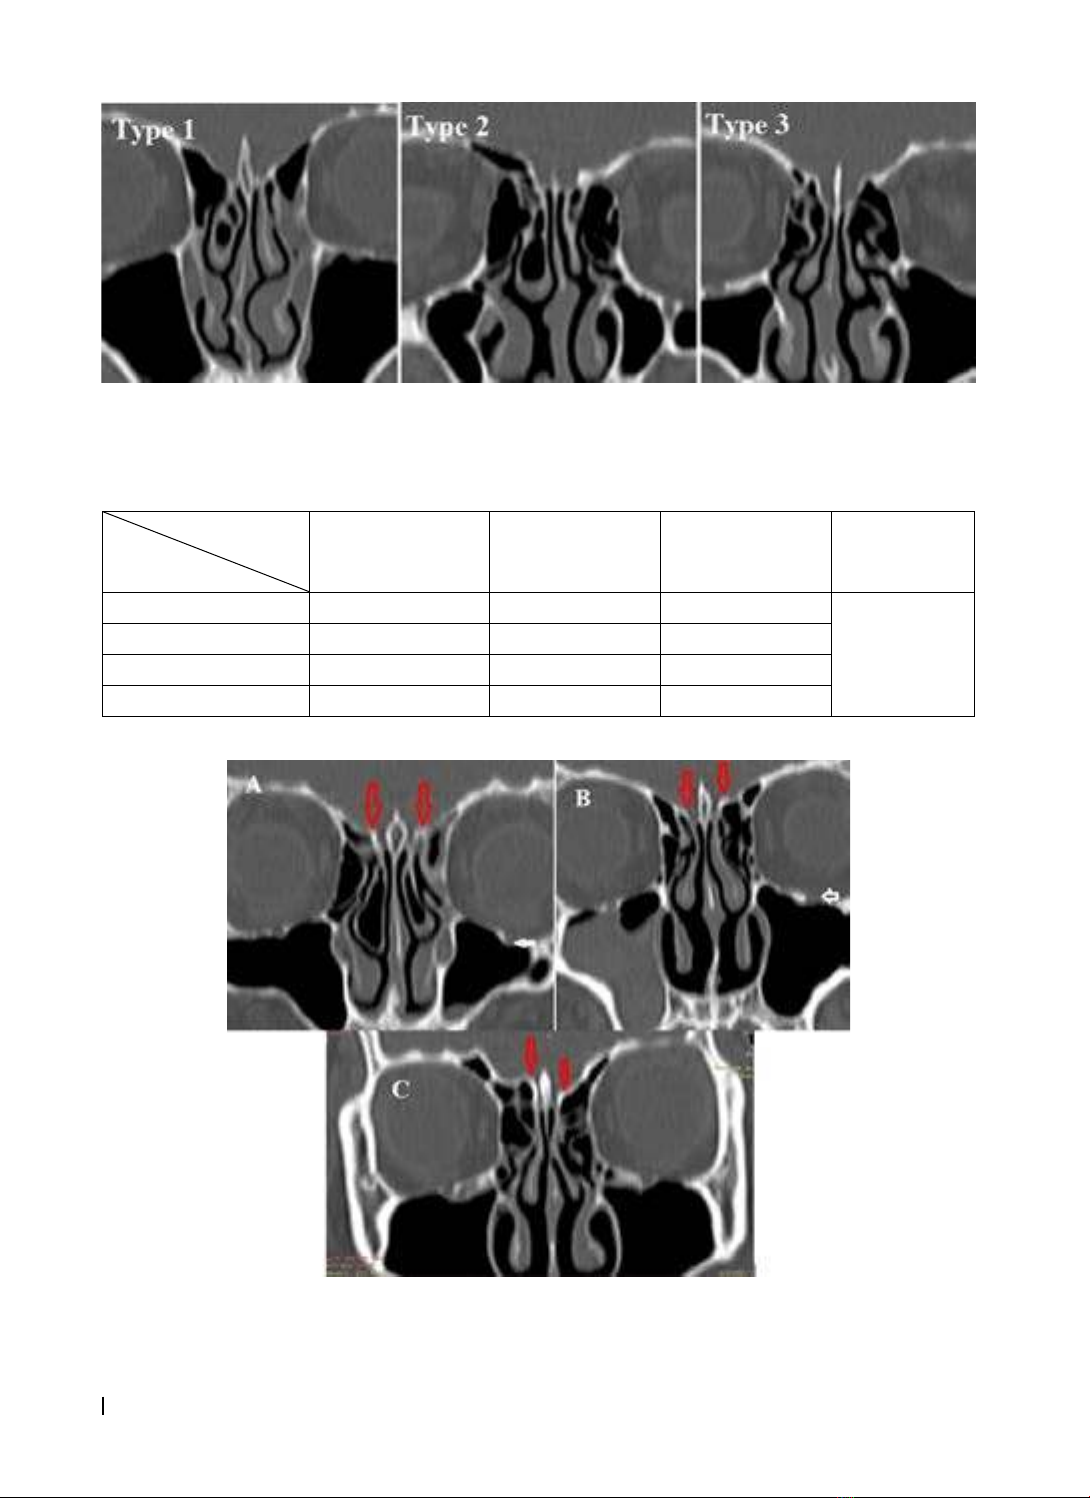

Hình 3.1. Phân loại Keros type 1 (BN N.L.T., ID: 3807), type 2 (BN L.T.K.S., ID: 3464), type 3 (BN Đ.V.S., ID: 4015)

Hình 3.2. A: Hai bên Keros 1, chênh lệch ≤ 1mm (BN L.T.H.E., ID: 3385). B: Bên phải Keros 1, bên trái Keros 2,

chệnh lệch 1-2mm (BN N.T.L., ID: 3758). Bên phải Keros 3 bên trái Keros 1, chênh lệch > 2mm